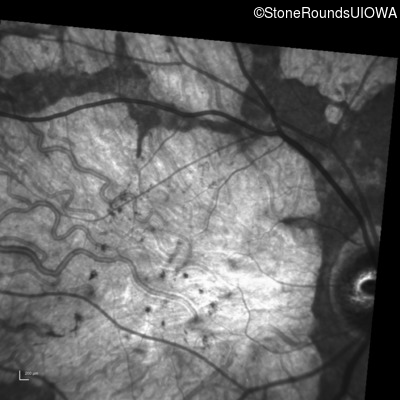

Blue Autofluorescence - Right - 10/125 sc

Exemplar

Blue Autofluorescence - Left - 10/125 +1 sc